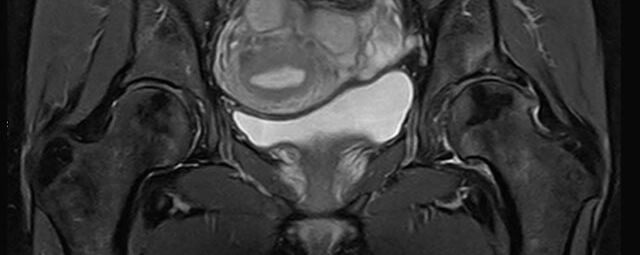

- Urogenitalorgane

- Tumordiagnostik z.B. im Bereich der Ovarien, des Uterus, der Prostata oder Harnblase

- dynamische MR-Analyse bei Beckenbodeninsuffizienz